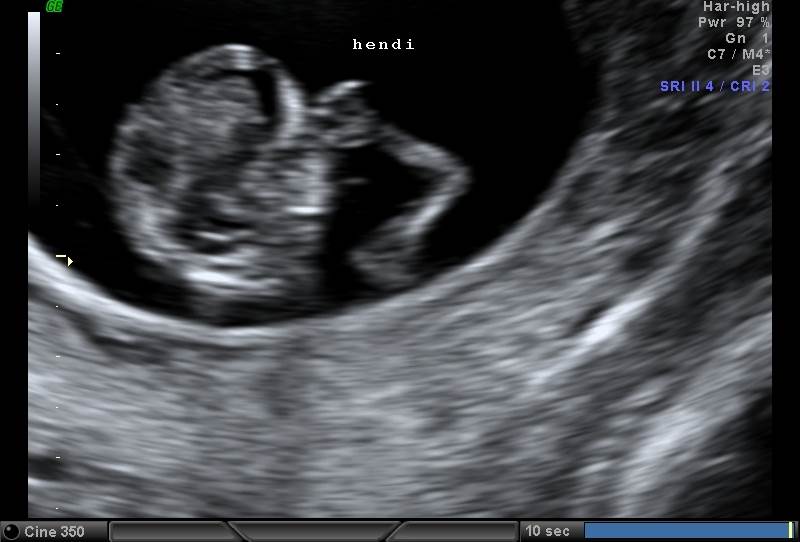

Hin nýja fósturgreiningardeild er mjög vel búin tækjum og til þess hefur hún meðal annars notið dyggs stuðnings Hringsins. |